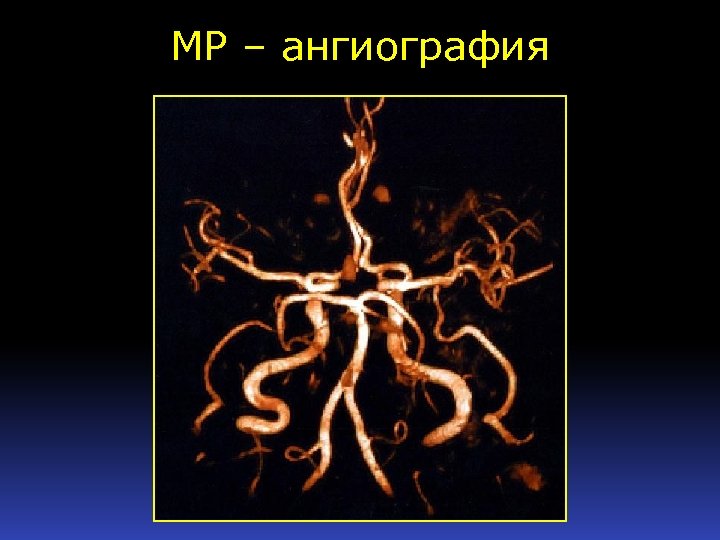

МР – ангиография

МР – ангиография